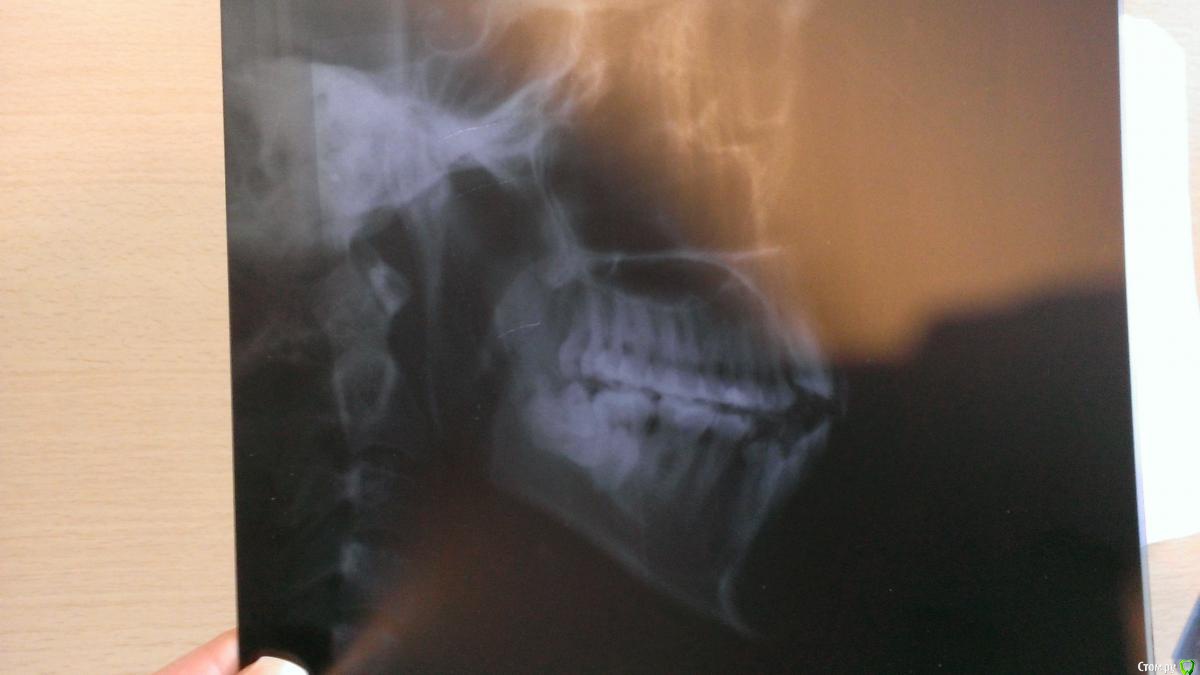

milhki Опубликовано 18 января, 2016 Поделиться Опубликовано 18 января, 2016 (изменено) Здравствуйте, уважаемые врачи! У меня к вам вопрос: как в моем случае лучше удалять нижние восьмерки с использованием пьезо или нет? Под общим наркозом или местным? Вопрос цены не стоит, главное, чтобы все прошло удачно и как можно менее травматично как физически, так и морально))) Летом 2015 начал беспокоить сустав справа, рот сильно широко и долго держать не могу. Насколько сложное удаление и на что надо обратить внимание? Спасибо! Снимки 2015 и 2009 года. Что с семеркой справа? Ее тоже надо будет удалять или полечить возможно, пока она меня никак не беспокоит, но врачи на нее указывали. Снимки худшего качества - лето 2015 года Снимок более темный - 2009 год Изменено 18 января, 2016 пользователем milhki Ссылка на комментарий